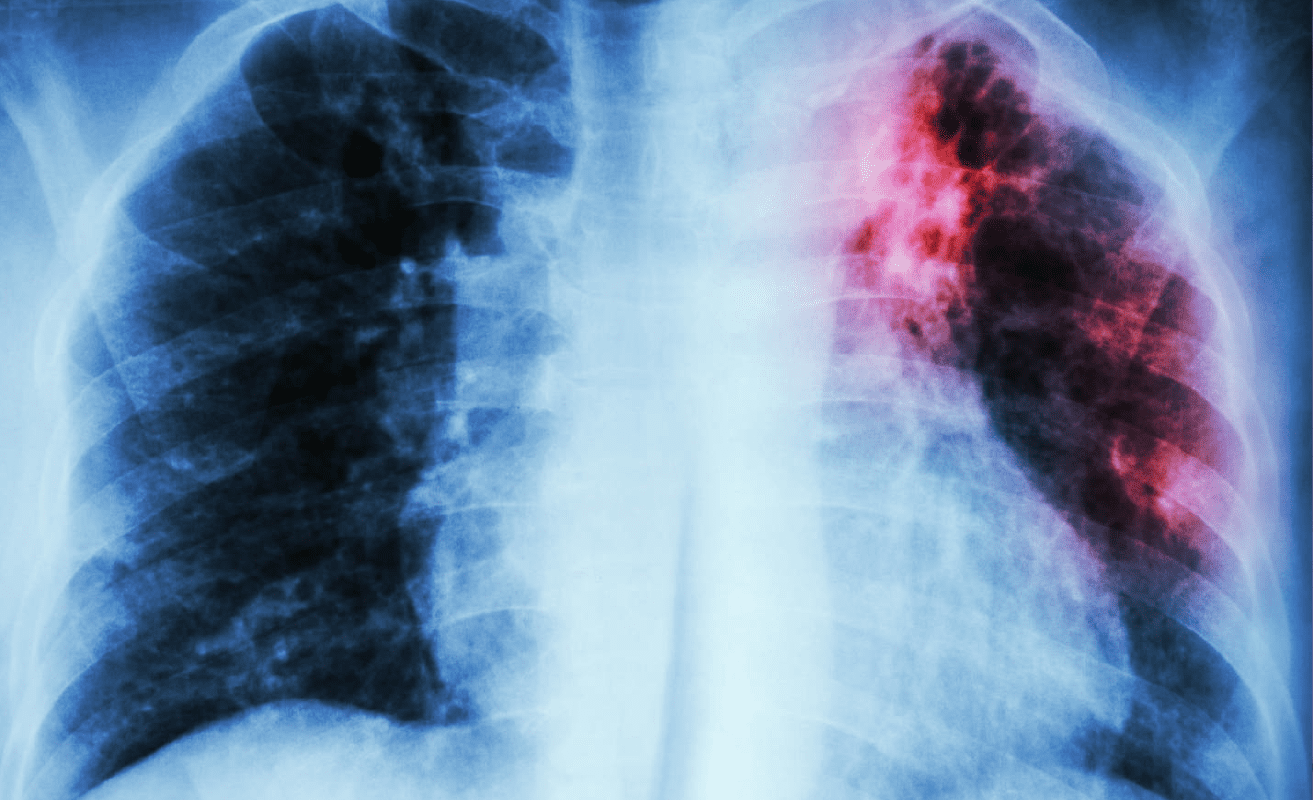

La Asociación Argentina de Medicina Respiratoria (AAMR) estima que el 70% de las personas que padecen la  Enfermedad Pulmonar Obstructiva Crónica (EPOC) no lo saben. Además, la organización advirtió que en el país hay alrededor de 2,3 millones de personas podrían padecer la enfermedad.

Según el estudio Epocar, realizado en seis conglomerados del país, sólo un 22% de los diagnosticados en dicho estudio se reconocían como pacientes con EPOC, lo que indicó que el subdiagnóstico roda más del 70%, fenómeno que se replica a nivel global.

Según la Organización Mundial de la Salud (OMS), la EPOC es la tercera causa de muerte en el mundo y la séptima de deficiencias de salud (medida por años de vida ajustados en función de la discapacidad).

El principal factor de riesgo es el tabaquismo y la edad promedio en todos los estudios es alrededor de los 60 años.

Los síntomas respiratorios son crónicos y suelen manifestarse con la sensación de falta de aire, tos e infecciones respiratorias con frecuencia y, a medida que avanza, los pacientes pueden sufrir exacerbaciones o agudizaciones de los síntomas.